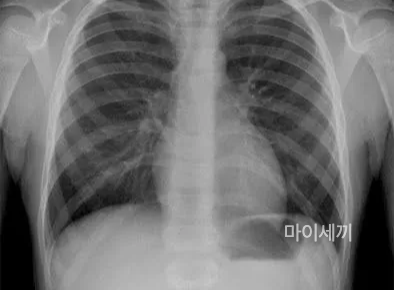

X-ray 검사

폐결핵의 진단은 흉부 X-선 검사를 통해 이루어집니다. 이를 위해 환자의 상태를 확인하고 약물 치료에 사용할 약제를 선택하며, 치료 과정 중에 사용할 약물의 금기 사항을 확인하는 여러 검사가 수행됩니다. 정기적으로 흉부 X-선 사진 촬영과 객담 검사를 반복하여 진행됩니다.